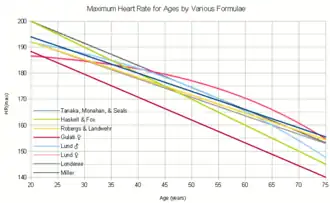

Maximum heart rate

The maximum heart rate (HRmax) is the age-related highest number of beats per minute of the heart when reaching a point of exhaustion[28][29] without severe problems through exercise stress.[30] In general it is loosely estimated as 220 minus one's age.[31] The maximum heart rate decreases with aging regardless of fitness, gender or diet.[32][31] Since HRmax varies by individual, the most accurate way of measuring any single person's HRmax is via a cardiac stress test. In this test, a person is subjected to controlled physiologic stress (generally by treadmill or bicycle ergometer) while being monitored by an electrocardiogram (ECG). The intensity of exercise is periodically increased until certain changes in heart function are detected on the ECG monitor, at which point the subject is directed to stop. Typical duration of the test ranges ten to twenty minutes. Adults who are beginning a new exercise regimen are often advised to perform this test only in the presence of medical staff due to risks associated with high heart rates.

The theoretical maximum heart rate of a human is 300 bpm; however, there have been multiple cases where this theoretical upper limit has been exceeded. The fastest human ventricular conduction rate recorded to this day is a conducted tachyarrhythmia with ventricular rate of 600 beats per minute,[33] which is comparable to the heart rate of a mouse.

For general purposes, a number of formulas are used to estimate HRmax. However, these predictive formulas have been criticized as inaccurate because they only produce generalized population-averages and may deviate significantly from the actual value. (See § Limitations.)

| Name | Data | HRmax Formula | Error |

|---|---|---|---|

| Haskell & Fox (1971)[34][35] | 35 data points | 220 − age | SD = 12–15 bpm[36] |

| Inbar, et al. (1994)[37] | 1424 men | 205.8 − (0.685 × age) | SD = 6.4 bpm |

| Tanaka, Monahan, & Seals (2001)[38] | 315 studies, 514 individuals | 208 − (0.7 × age) | SD ~10 bpm |

| Wohlfart, B. and Farazdaghi, G.R.[39][40] | 81 men, 87 women | Men: 203.7 / ( 1 + exp( 0.033 × (age − 104.3) ) ) Women: 190.2 / ( 1 + exp( 0.0453 × (age − 107.5) ) ) |

SD = 6.5% men, 5.5% women |

| Oakland University (2007)[41] | 100 men, 32 women, 908 longitudinal observations | Linear: 207 − (0.7 × age) Nonlinear: 192 − (0.007 × age2) |

1 SD confidence interval: ±5–8 bpm (linear), ±2–5 bpm (nonlinear) |

| Gulati (2010)[42] | 5437 women | Women: 206 − (0.88 × age) | SD = 11.8 bpm |

| Nes, et al. (2013)[43] | 1726 men, 1594 women | 211 − (0.64 × age) | SEE = 10.8 bpm |

| Wingate (2015)[44] | 20,691 males, 7446 females | Men: 208.609–0.716 × age Women: 209.273–0.804 × age |

SD = 10.81 (male), 12.15 (female) |

Haskell & Fox (1970)

Notwithstanding later research, the most widely cited formula for HRmax is still:[45]

- HRmax = 220 − age

Although attributed to various sources, it is widely thought to have been devised in 1970 by Dr. William Haskell and Dr. Samuel Fox.[46] They did not develop this formula from original research, but rather by plotting data from approximately 11 references consisting of published research or unpublished scientific compilations.[35] It gained widespread use through being used by Polar Electro in its heart rate monitors,[46] which Dr. Haskell has "laughed about",[46] as the formula "was never supposed to be an absolute guide to rule people's training."[46]

While this formula is commonly used (and easy to remember and calculate), research has consistently found that it is subject to bias, particularly in older adults.[47] Compared to the age-specific average HRmax, the Haskell and Fox formula overestimates HRmax in young adults, agrees with it at age 40, and underestimates HRmax in older adults.[43][44] For example, in one study, the average HRmax at age 76 was about 10bpm higher than the Haskell and Fox equation.[44] Consequently, the formula cannot be recommended for use in exercise physiology and related fields.[35]

Other formulas

HRmax is strongly correlated to age, and most formulas are solely based on this.[38] Studies have been mixed on the effect of gender, with some finding that gender is statistically significant, although small when considering overall equation error, while others finding negligible effect.[44] The inclusion of physical activity status, maximal oxygen uptake, smoking, body mass index,[43] body weight, or resting heart rate[41] did not significantly improve accuracy. Nonlinear models are slightly more accurate predictors of average age-specific HRmax, particularly above 60 years of age, but are harder to apply, and provide statistically negligible improvement over linear models.[41][44] The Wingate formula is the most recent, had the largest data set, and performed best on a fresh data set when compared with other formulas, although it had only a small amount of data for ages 60 and older so those estimates should be viewed with caution.[44] In addition, most formulas are developed for adults and are not applicable to children and adolescents.[48]

Limitations

Maximum heart rates vary significantly between individuals.[46] Age explains only about half of HRmax variance.[44] For a given age, the standard deviation of HRmax from the age-specific population mean is about 12bpm, and a 95% interval for the prediction error is about 24bpm.[49] For example, Dr. Fritz Hagerman observed that the maximum heart rates of men in their 20s on Olympic rowing teams vary from 160 to 220.[46] Such a variation would equate to an age range of -16 to 68 using the Wingate formula.[50] The formulas are quite accurate at predicting the average heart rate of a group of similarly-aged individuals, but relatively poor for a given individual.

Robergs and Landwehr opine that for VO2 max, prediction errors in HRmax need to be less than ±3 bpm. No current formula meets this accuracy. For prescribing exercise training heart rate ranges, the errors in the more accurate formulas may be acceptable, but again it is likely that, for a significant fraction of the population, current equations used to estimate HRmax are not accurate enough.[35] Froelicher and Myers describe maximum heart formulas as "largely useless".[51] Measurement via a maximal test is preferable whenever possible,[43] which can be as accurate as ±2bpm.[35]